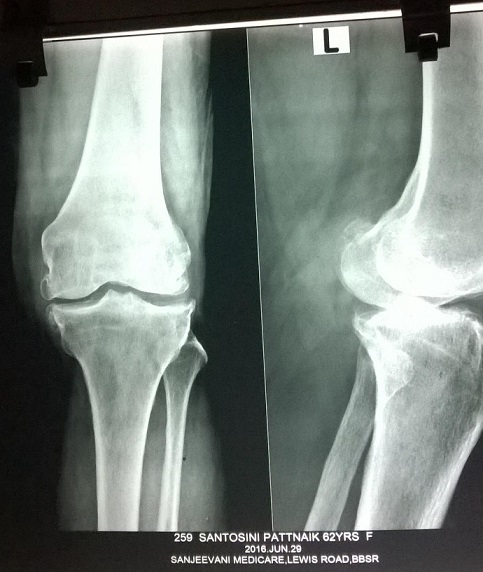

X-Ray of Santosini Pattanayak

This is a case of Anterior crusateligame reconstruction. After which the patient had a non healing wound for which, debridement was done. But no improvement. Suffered for one year. Now, After Laser Treatment, she has recovered completely.